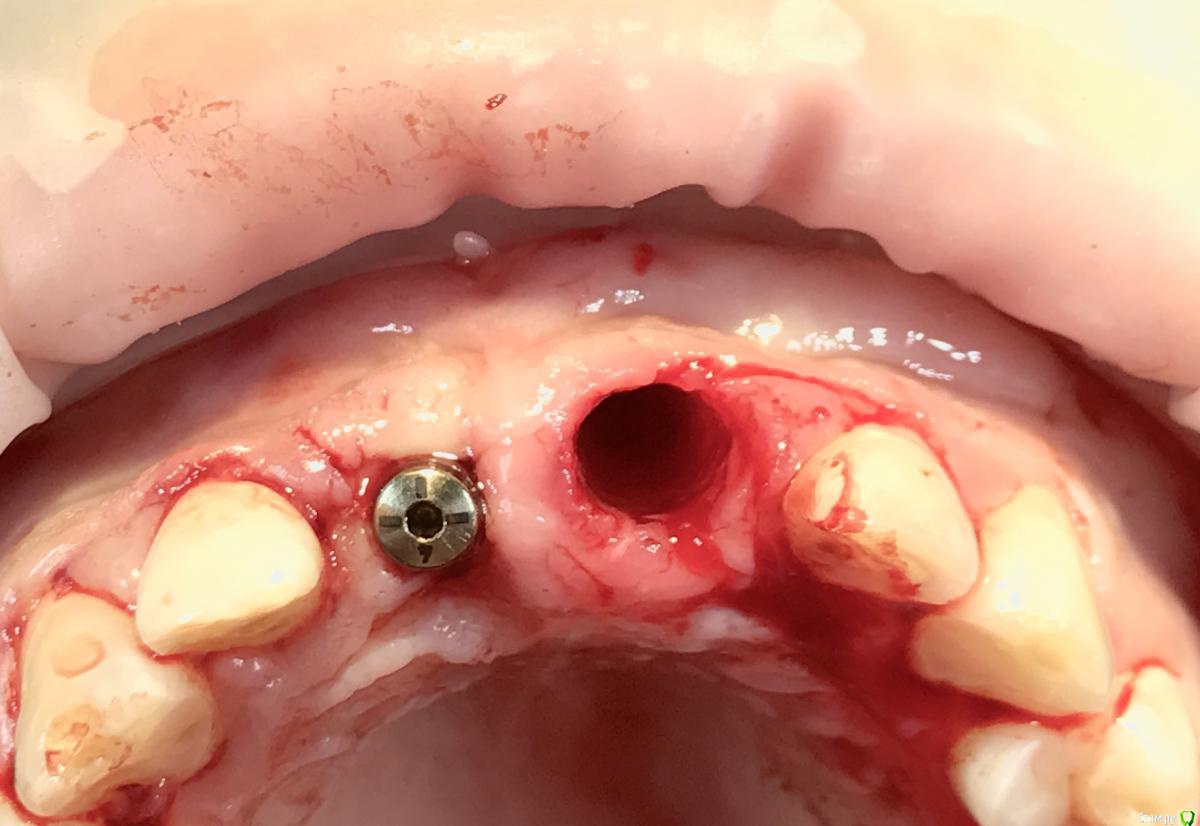

Bier Опубликовано 16 марта, 2018 Поделиться Опубликовано 16 марта, 2018 Зубы были удалены 2 месяца назад. Как быть? 1 Ссылка на комментарий

Bier Опубликовано 16 марта, 2018 Автор Поделиться Опубликовано 16 марта, 2018 ну вроде кортикалка сохранена, можно ставитьтолько в области 22з Ссылка на комментарий

Bier Опубликовано 17 марта, 2018 Автор Поделиться Опубликовано 17 марта, 2018 А в чем сложность?пластику делаем/ не делаем? Одномоментно/отсрочено? Какой имплантат выбрать? Ссылка на комментарий

колесников Опубликовано 18 марта, 2018 Поделиться Опубликовано 18 марта, 2018 Июль-ноябрь. Вестибулярная компактная пластинка отсутствует на всю длину импланта. Ссылка на комментарий

Irouil Опубликовано 18 марта, 2018 Поделиться Опубликовано 18 марта, 2018 Я бы пробовал расширить гребень в 2.1, цервикально будет дефект, край кости миллиметрах в 7 (линейки нет, на глаз) будет от цэс. С профайлом не работаю, может реально хватит, но я бы 3.0 поставил астру, дальше собрал стружки откуда-то (пробовал бы из под носовой ости), усыпал немного, укрыл, сверху бы десневой трансплантат, часть деэпитилизировал и под вестибулярный лоскут, остальным заглушил. С 2.2 наверное просто имплантат и стт вестибулярно и интерпроксимально Не знаю что будет с сосочками, прогноз на вестибулярку 2.1 не надёжный. Ссылка на комментарий